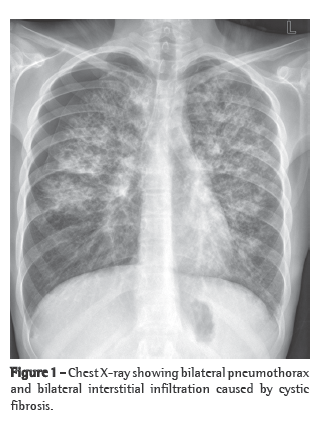

Based on the tomographic findings, we decided to investigate PVOD using bronchoscopy and bronchoalveolar lavage (BAL). The cytological analysis revealed a predominance of macrophages (89% of the total number of cells), 50% of which were hemosiderin-laden (Figure 2). Therefore, the presumptive diagnosis was PVOD.

Dou to the predominance of the postcapillary component, occult alveolar hemorrhage, as evidenced by hemosiderosis, is considered another characteristic of PVOD.(3) It has recently been demonstrated that the quantification of hemosiderin-laden macrophages in BAL fluid can be used as a means of differentiating between patients with PVOD and those with idiopathic pulmonary hypertension Since such patients present functional limitation, and since surgical lung biopsy implies considerable morbidity and mortality, a presumptive diagnosis of PVOD should be made based on the combination of suggestive tomographic findings and BAL-proven occult alveolar hemorrhage.